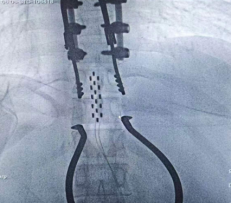

2026年1月30日,完善術(shù)前準(zhǔn)備后,手術(shù)于全麻并全程電生理監(jiān)測下進(jìn)行,歷經(jīng)5小時苦戰(zhàn),順利于腰膨大處置入外科電極一枚,雙側(cè)骶3孔各植入一根穿刺電極,連接2枚刺激器后埋置于皮下。手術(shù)實(shí)施順利,術(shù)中X線檢查植入位置良好。目前患者生命體征平穩(wěn),已開機(jī)測試,后期動態(tài)調(diào)整刺激參數(shù),并結(jié)合非侵入式腦機(jī)接口鍛煉。

成功植入565外科電極

雙側(cè)骶3孔順利植入穿刺電極